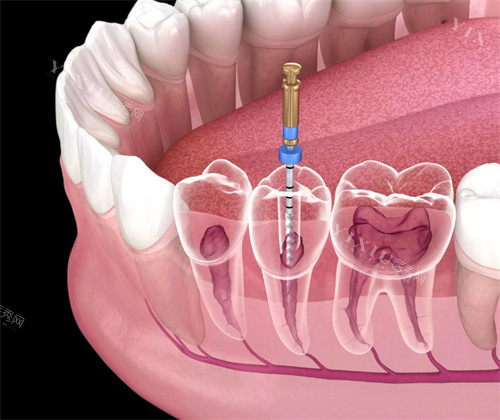

非手术再治疗:

化学辅助疏通:使用EDTA等螯合剂软化钙化组织

超声器械应用:配合特殊冲洗液震荡松解堵塞物

显微根管技术:在放大视野下精细操作

机械疏通:采用改良预备技术逐步扩通